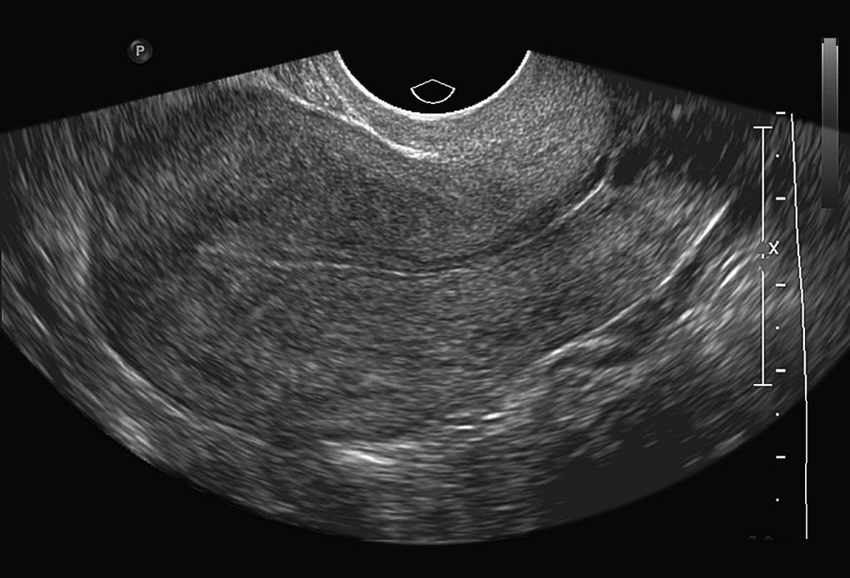

The PCOS ultrasound image dataset was collected from Kaggle [39]. The data folder consists of ’train’ and ’test’ subfolders, each containing two categories: ’infected’ and ’notinfected’. The infected folder contains images of ovaries with PCOS, while the notinfected folder contains images of healthy ovaries. In the train directory, the infected folder contains 781 images, and the notinfected folder contains 1,143 images. The test directory includes 787 infected images and 1,145 noninfected images. Figure 2 illustrates ultrasound scans of both infected and noninfected ovaries. Visual differences between infected and noninfected ovaries are apparent. In Figure 2(a), the ultrasound image shows characteristic holes (follicles), which distinguish it from Figure 2(b) (noninfected), where no such holes are present.

(a) Infected Ultrasound Image

(b) Noninfected Ultrasound Image

Figure 2: PCOS infected and noninfected ultrasound images